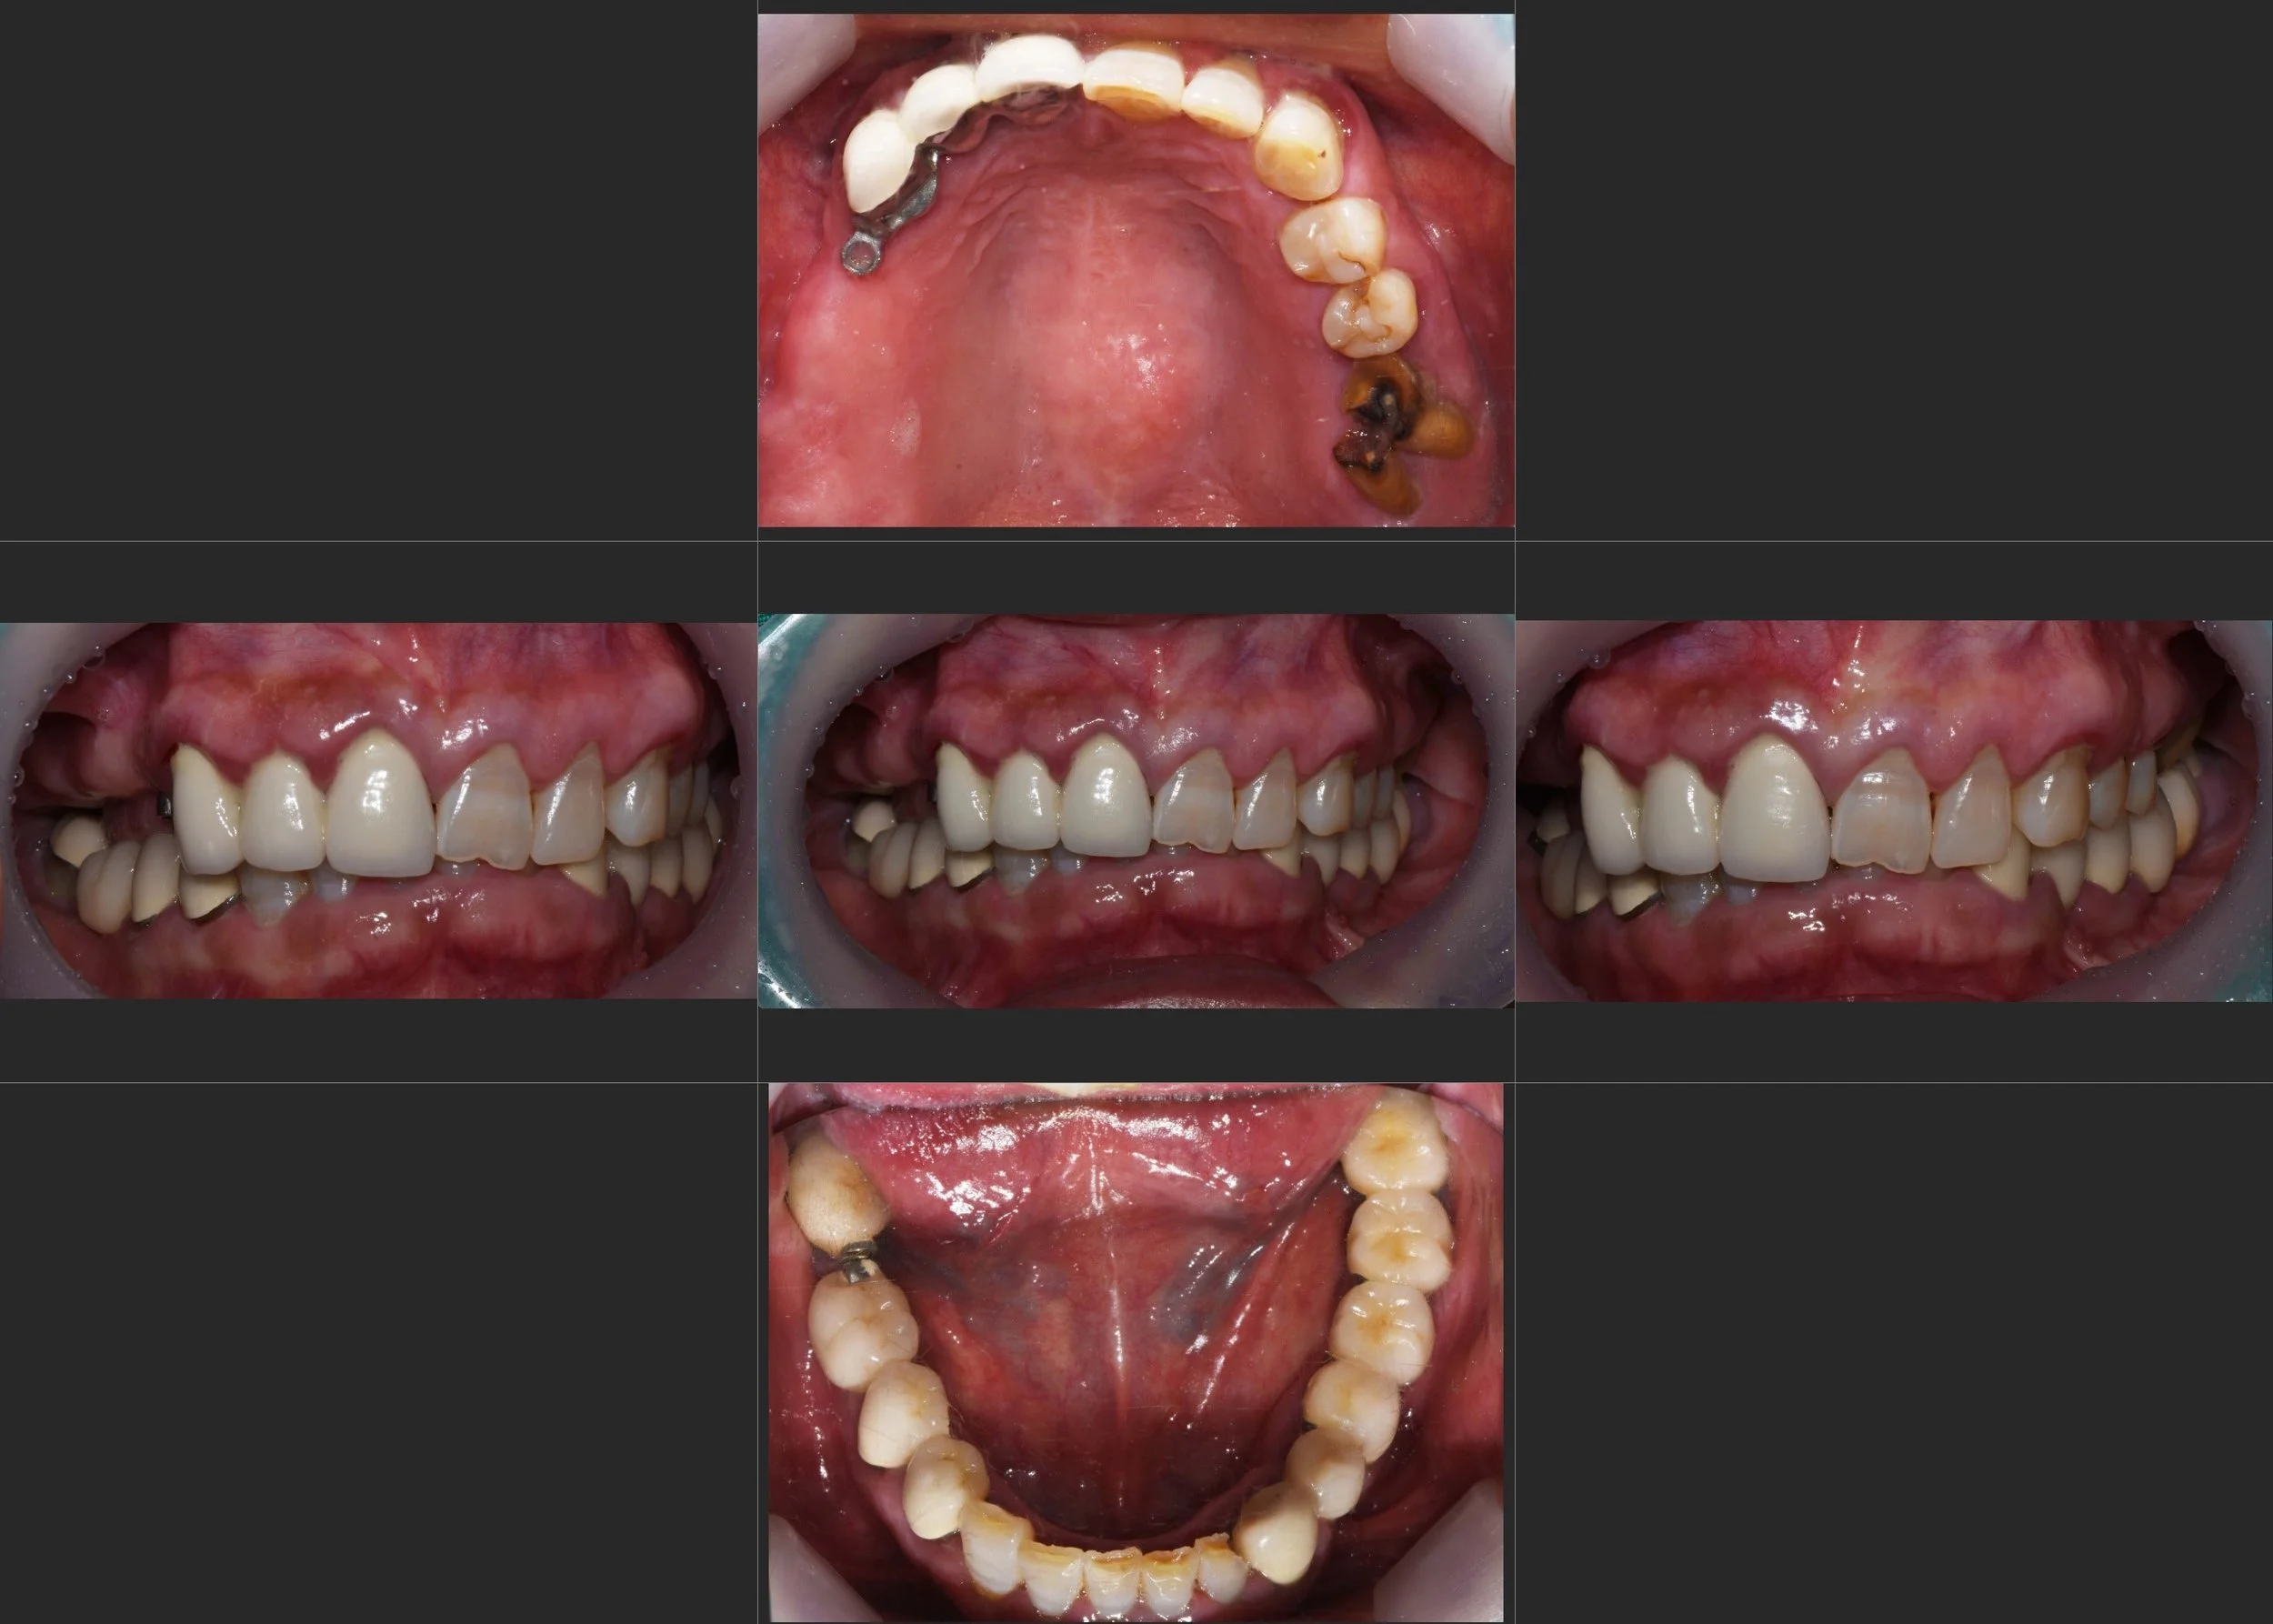

INTRA ORAL - BEFORE

The patient had discontinued use of an ill-fitting removable denture and relied on unilateral mastication over an extended period.

As a result, the contralateral dentition deteriorated, leading to progressive occlusal collapse and aesthetic concerns.

Despite the compromised occlusion, the patient wished to preserve an existing fixed bridge for financial reasons.

• Restoration of anterior restorative space through controlled occlusal vertical increase

• Improvement of dental aesthetics while maintaining existing restorations where possible

• Redistribution of occlusal forces to reduce overload on compromised teeth

• Establishment of a maintainable occlusal scheme for both existing and newly placed prostheses